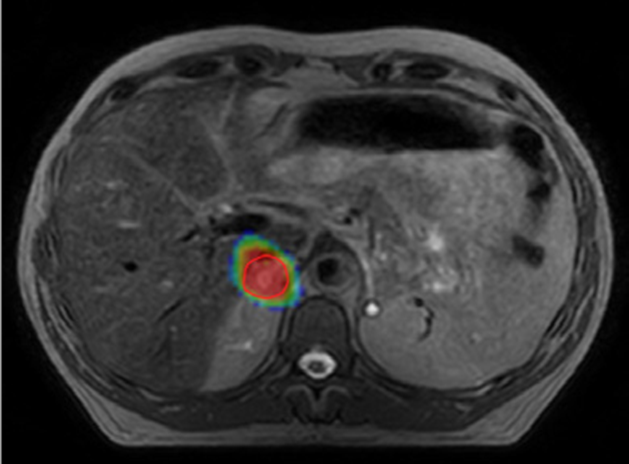

Key studies show that high-dose, image-guided SBRT delivers the stronger doses kidney tumors require, providing durable control with low side effects.

Kidneys can move by as much as 4 cm during normal breathing, so daily imaging and motion control are essential for accurate treatment and healthy-tissue protection.13

Across multiple trials, SBRT achieved 96% two-year and 91% four-year cancer-specific survival, with no grade 3–5 side effects, matching surgical outcomes for selected patients.12

If surgery isn’t possible for people with localized kidney cancer, stereotactic MR-guided adaptive radiotherapy offers a safe, noninvasive treatment option with minimal impact on kidney function.11